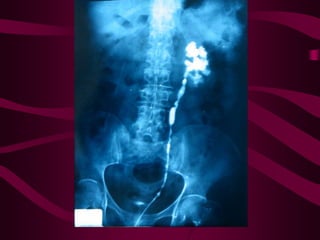

Este documento describe la tuberculosis genitourinaria. Afecta más a hombres que a mujeres. Se transmite principalmente a través de la infección pulmonar primaria y luego se disemina a través de la sangre a los riñones u otros órganos. Causa lesiones como granulomas y necrosis si no se controla, lo que puede provocar complicaciones como abscesos e insuficiencia renal. Se diagnostica mediante pruebas de orina y tratamiento con medicamentos durante varios meses.